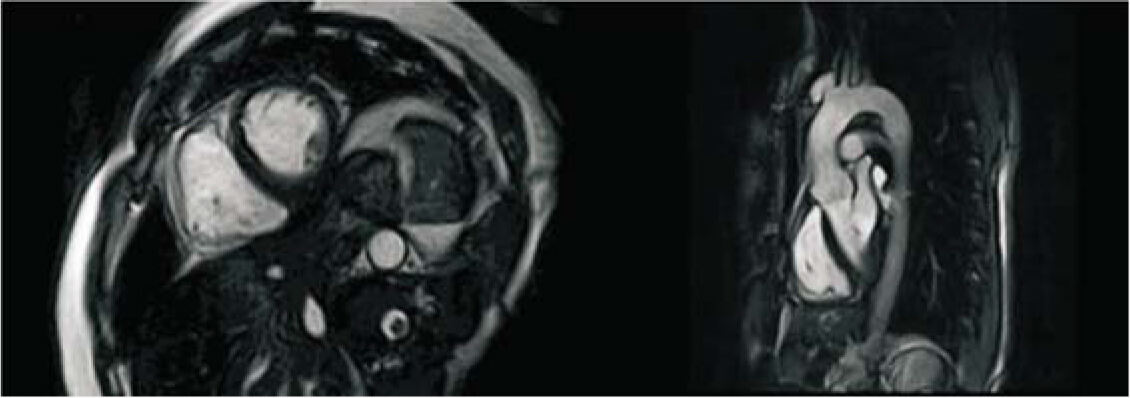

SuperMark 1.5T is a latest generation superconducting MRl system based on over 30 years of experience in research and development, which focuses on user's concerns. This system is equipped with a new upgraded hardware and software platforms with A-combi and Al technologies that benefit users a lot and deliver patients with more comfortable experiences. It features new user-friendly design, faster imaging speed, higher image quality and greatly improved work efficiency.

SuperMark 1.5T provides not only conventional pulse sequences and basic clinical applications, but also advanced functional applications. Moreover, it adopts brand new professional APEX operation system which ensures easy operation and fast diagnosis